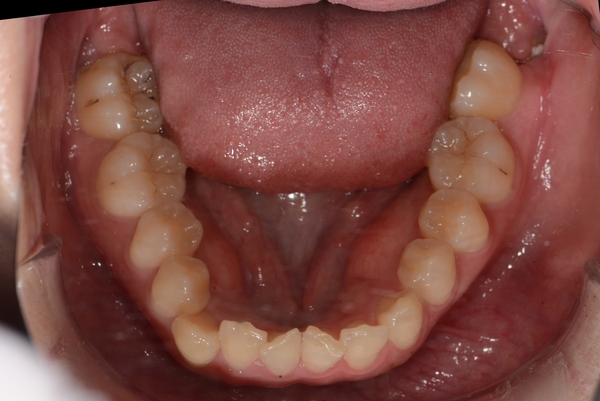

ガタガタとした歯並びや八重歯(叢生)CASE63